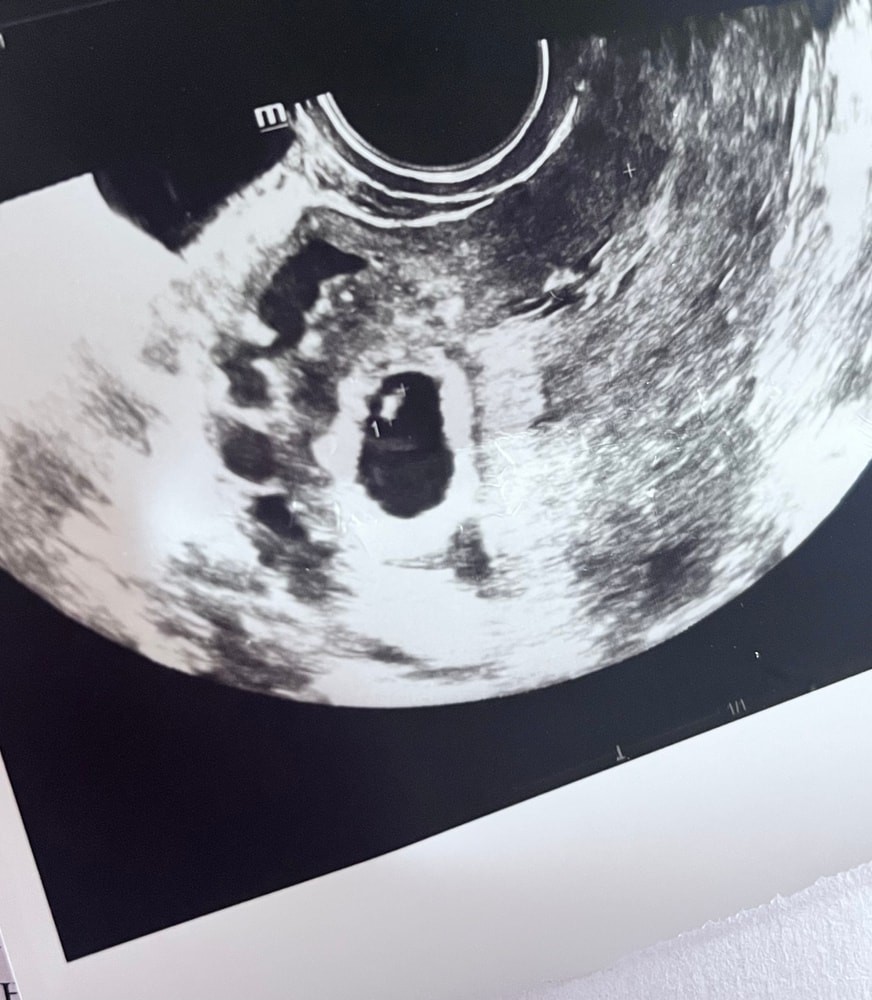

Сердцебиение 109 на 6 неделе

Сегодня ходила на узи

свд 11,5мм

эмбрион 3,5 мм

желточный мешок 5 мм

сердцебиение 109 уд/мин

Поставили срок 6 недель

Первое узи делала 10.07. Там просто написали свд 5 мм срок 4-5 нед